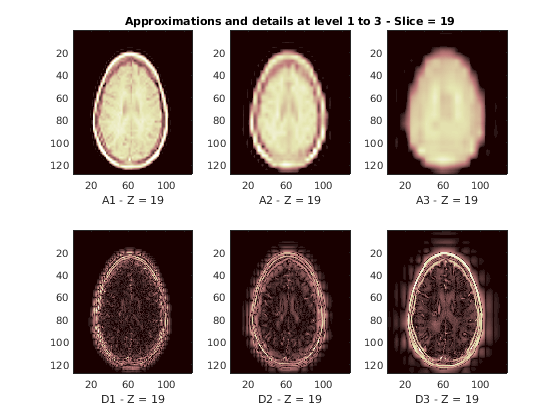

Восстановленные приближения и детали вдоль Z-ориентации отображены ниже.

nbIMG = 6; idxImages_New = [1 7 10 16 19 25]; for ik = 1:nbIMG j = idxImages_New(ik); figure('DefaultAxesXTick',[],'DefaultAxesYTick',[],... 'DefaultAxesFontSize',8,'Color','w') colormap(map) for k = 1:n labstr = [int2str(k) ' - Z = ' int2str(j)]; subplot(2,n,k); image(A{k}(:,:,j)); xlabel(['A' labstr]); if k==2 title(['Approximations and details at level 1 to 3 - Slice = ' num2str(j)]); end subplot(2,n,k+n); imagesc(abs(D{k}(:,:,j))); xlabel(['D' labstr]); end end